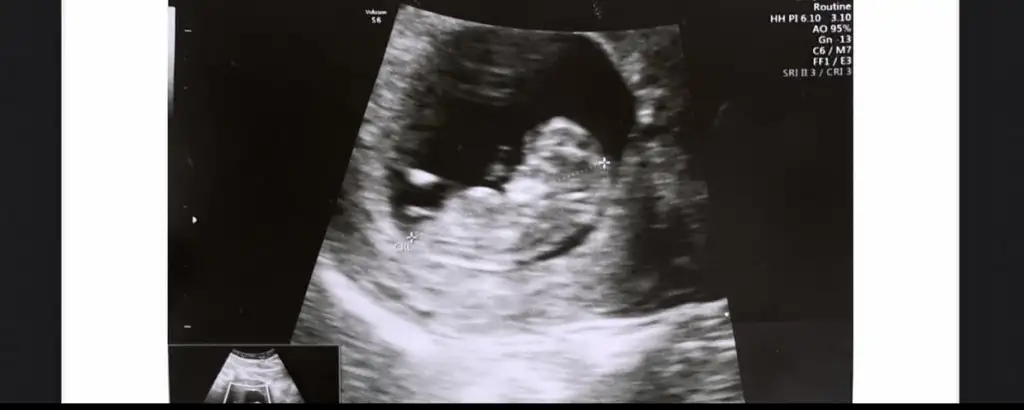

5 ve 14. haftaya kadar olan ultrasyon fotolarınızı paylaşın. Vajinadan mı yoksa karından mı çekildiğini ve kaç haftalık olduğunu da mutlaka belirtin.

Vajinal bakildi. 7. Haftadayim.karından mı? kaç haftalık?